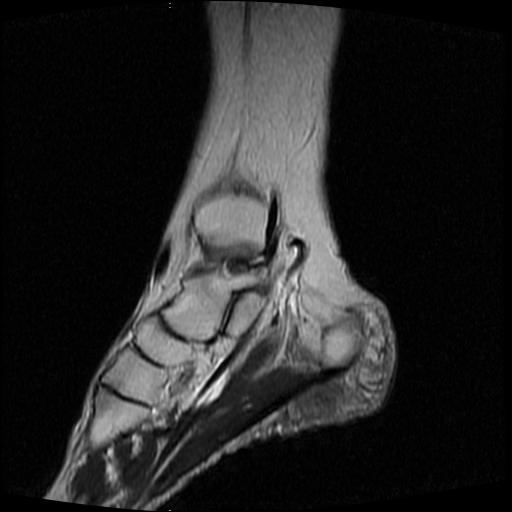

女性,70岁,右侧跟骨疼痛2个月,负重时加剧,不负重时不疼。

胫骨下段,跟骨、距骨可见斑片状异常信号区;考虑:转移瘤

跟骨长t1长t2信号异常,边缘模糊(肿瘤一般边界清楚,故肿瘤不考虑),压脂像呈高信号--骨髓水肿(炎症?)。